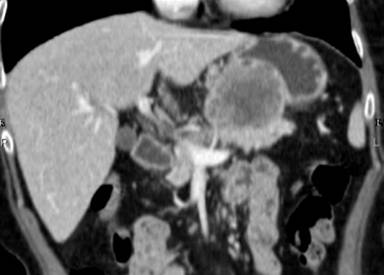

An endoscopy of the upper gastrointestinal tract showed a submucosal tumor, about 4 cm in diameter, located in the posterior wall of the gastric body (Figure 1). The results of the bioptic specimen could not be diagnosed pathologically. MRCP showed neither dilation nor irregularity of the main pancreatic duct (Figure 2). A CT scan demonstrated an ill-defined, irregular solid mass, 6x6x7 cm in size, situated between the retroperitoneum, the pancreas and the lesser curvature of the stomach (Figure 3). The tumor seemed to originate from the retroperitoneum with invasion of the stomach and pancreas. The left gastric artery and the splenic artery were compressed by the tumor which was located adjacent to the celiac axis. Celiac angiography indicated encasement of the splenic artery (Figure 4). Superior mesenteric artery angiography and portography were unremarkable. The tumor was essentially hypovascular. Although a definitive diagnosis was uncertain on the basis of the imaging findings described above, primary neoplasms including malignant mesenchymal tumors were taken into consideration preoperatively.

Figure 3. Coronal image of an abdominal CT scan demonstrating an ill-defined, huge solid mass between the pancreas and the lesser curvature of the stomach. |